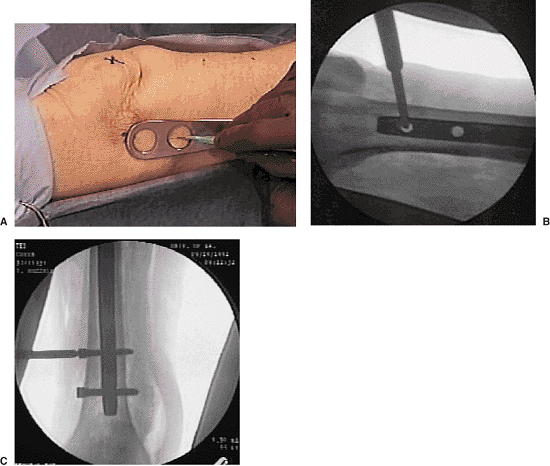

Figure 20.26. A–C.

Freehand technique: hole is located with external marker and a stab incision is made over the hole axis; the trocar is inserted to dimple bone; drilling is done for bicortical fixation; screws are inserted. |

decreases the incidence of shortening and malrotation. I prefer a

freehand technique or use a radiolucent drill guide for distal

interlocking-screw placement (Fig. 20.26).